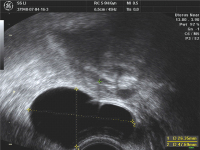

Embryotransfertechnik - Was ist für den Erfolg wichtig?

Journal für Reproduktionsmedizin und Endokrinologie - Journal of Reproductive Medicine and Endocrinology 2011; 8 (2): 123-129 Volltext (PDF) Summary Praxisrelevanz Abbildungen